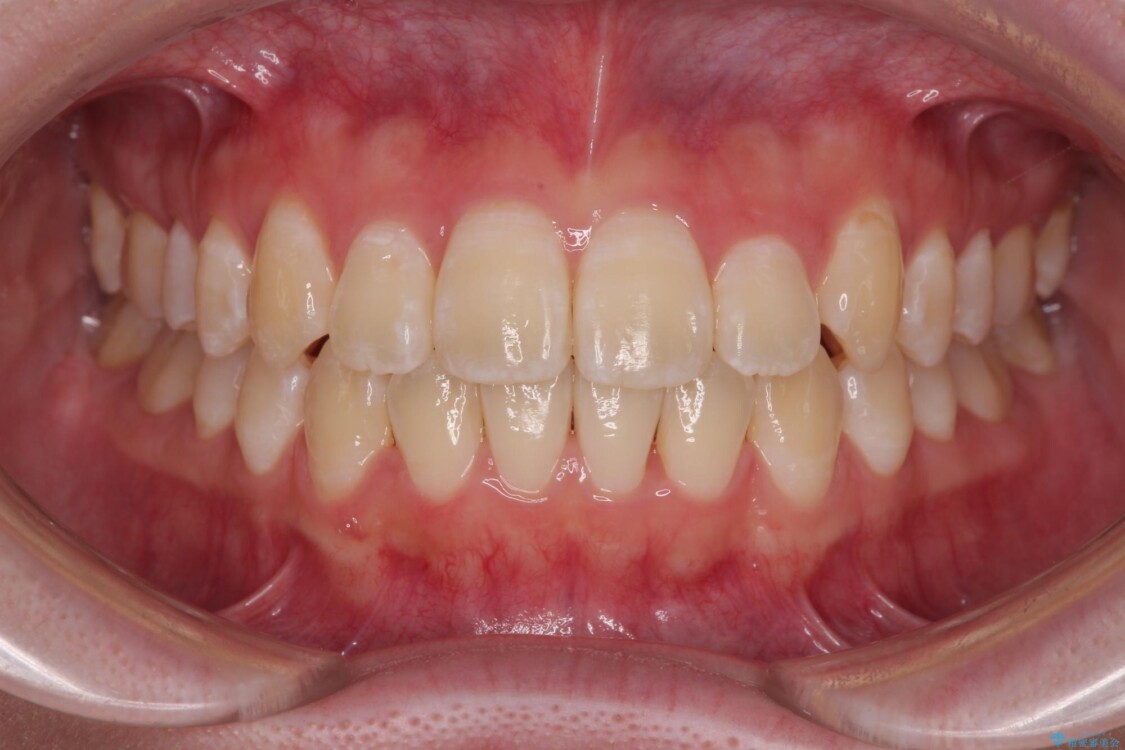

治療後

• 【モニター】前歯のデコボコをスッキリ解消!目立ちにくいワイヤー矯正でスピーディに治療完了 治療後画像

上下の正中(真ん中のライン)もずれることなく、バランスの取れた美しい歯並びに。笑顔に自信を持てる仕上がりとなりました。